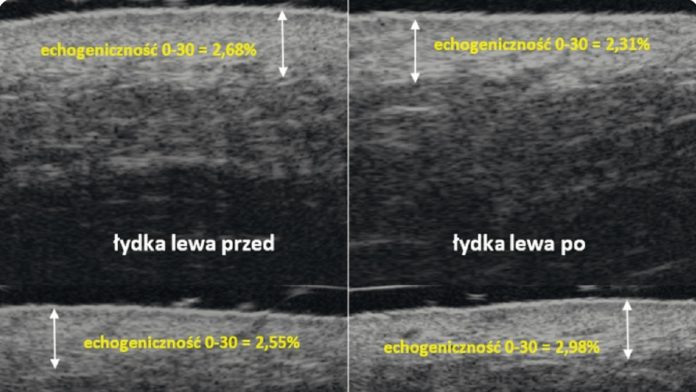

Celem niniejszej pracy było przedstawienie wyników badań dotyczących skuteczności preparatu nawilżającego, którego działanie oceniane było za pomocą ultrasonografii wysokich częstotliwości. Uzyskane wyniki potwierdziły, że zmiany w zakresie parametrów ujętych w badaniu mogą służyć do oceny skuteczności preparatu.

W oparciu o wyniki niniejszych badań można stwierdzić, że ultrasonografia jest użyteczną metodą w ocenie skuteczności działania preparatów kosmetycznych i może być powszechnie wykorzystywana w tym celu.

This study aimed to describe the findings about the effectiveness of a moisturiser, which was evaluated by highfrequency ultrasonography. The collected results have verified that modifications in the parameters examined can be utilised to assess the effectiveness of the preparation.

The results of this study support the conclusion that ultrasonography is a valuable technique for evaluating the effectiveness of cosmetic products and can be extensively employed for this purpose.